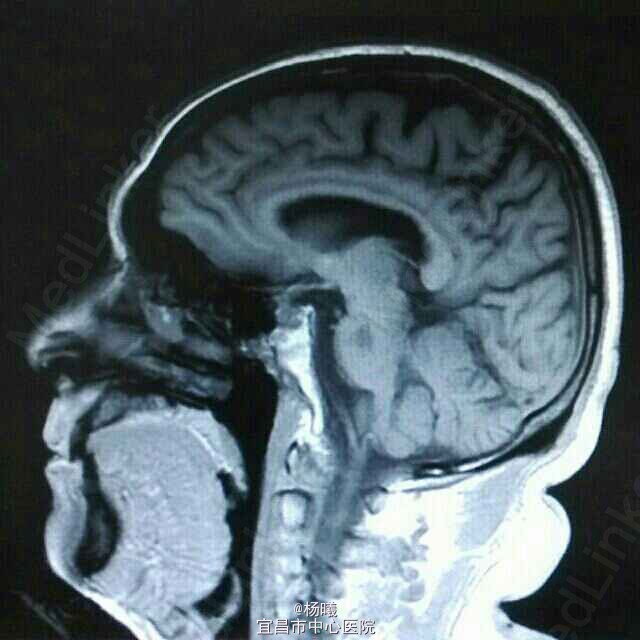

查体:BP 136/84mmHg,抬腿右下肢较左侧差,余无明显异常。 辅检:6-8 D-D 1.87,FIB 7.15,ALT 38,AST 46,GGT 37,LDL-C 4.38,铁蛋白 320,CRP 96.7,ESR 70,尿酮体1+ 6-15 PLT 469,ALT 53,GGT 50,ESR 38,D-D 0.59 血糖监测:早餐后高 彩超多普勒:升主动脉较宽,左室舒张功能减低;双侧颈动脉粥样硬化斑形成。 经颅多普勒:双侧颈内动脉、颈外动脉、左侧颈总动脉血流速度减慢;左侧锁骨下动脉、右侧大脑中动脉、大脑前动脉、左侧颈内动脉虹吸部管腔呈收缩状态;左侧颈内动脉虹吸部管腔重度狭窄;各检查动脉管腔应硬化。 头部MR、脑动脉造影MRA:脑干右侧11*12mm梗塞灶;腔隙性脑梗塞;脑萎缩;双侧额部顶部硬膜下积液;左侧椎动脉起始段及椎动脉-基底动脉汇合段管腔中度狭窄,双侧颈总、颈内外动脉、双侧大脑前中后动脉多发中-重度狭窄,动脉粥样硬化表现。

诊断:脑梗塞;高血压病3级 极高危;糖尿病 2型;动脉粥样硬化;高脂血症;慢性胃炎 治疗:依达拉奉、马来酸桂哌齐特、丹森川穹嗪注射,小牛血清去蛋白注射液;硝苯地平缓释片;阿司匹林肠溶片;阿托伐他丁钙片;阿卡波糖片。